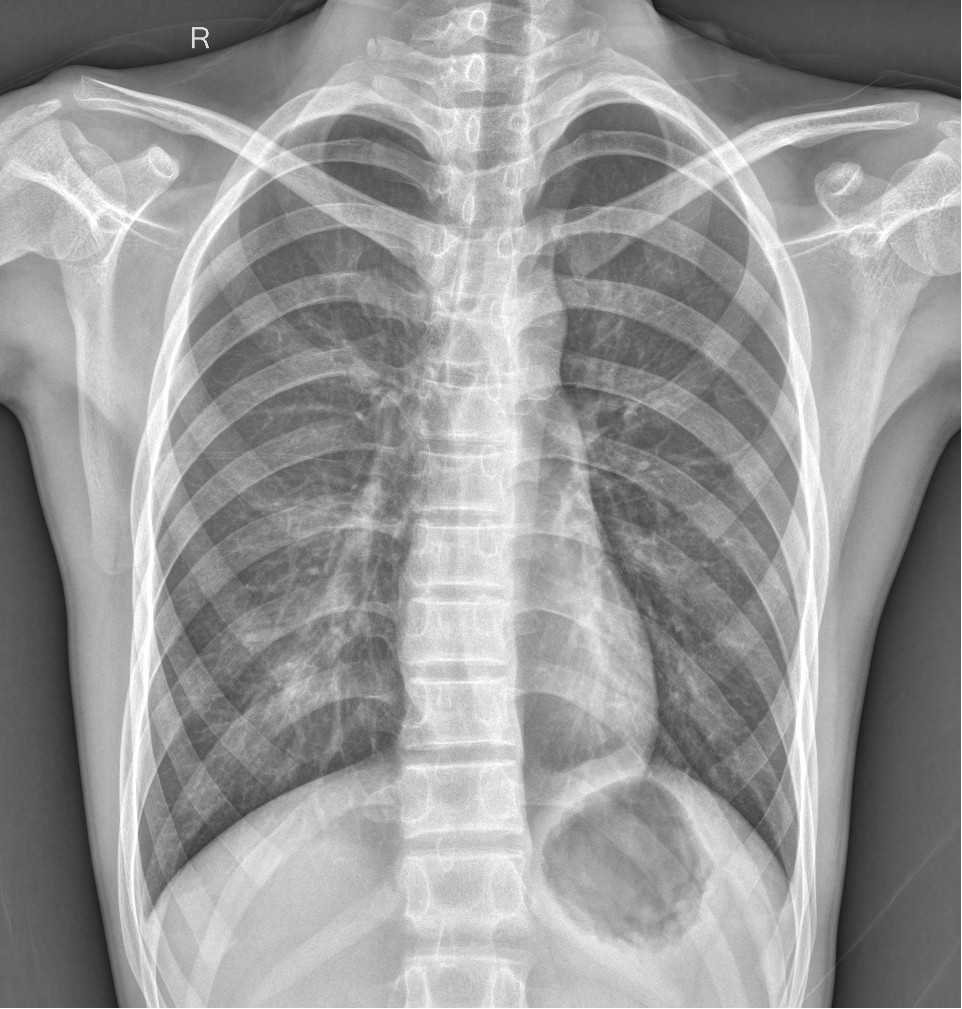

DR是最常用的X线检查技术,它是利用X射线的穿透能力生成从黑到白不同灰度的影像,也就是大家常说的“拍片”。

检查应用范围:骨骼系统、呼吸系统、循环系统、消化系统、泌尿系统等

优点:辐射剂量小,价格相对便宜,是疾病初筛的主要检查方式及骨关节系统的重要检查方法。

缺点:只能提供二维的平面影像,组织前后重叠且密度分辨率低,有些部位是看不见的,若需进一步观察,需要进行升级版的CT检查。

我们可以把人体组织想象成一块面包,DR检查是把面包压扁了来看。当X线穿过人体后,遇到被遮挡的部位,图像上是不会显示的。就像一片面包,看不到里面的纤维纹理,但是它的结构完整性更强。

DR和CT是两种不同的检查方法,其侧重点不同,各具优势,两者不能互相替代。比如对于骨折来说,DR诊断要比CT更好,因为DR可以直接排除绝大多数的骨折,但是对于隐形性的骨折,CT会更好一些,可以作为DR检查后的进一步定性检查方法。